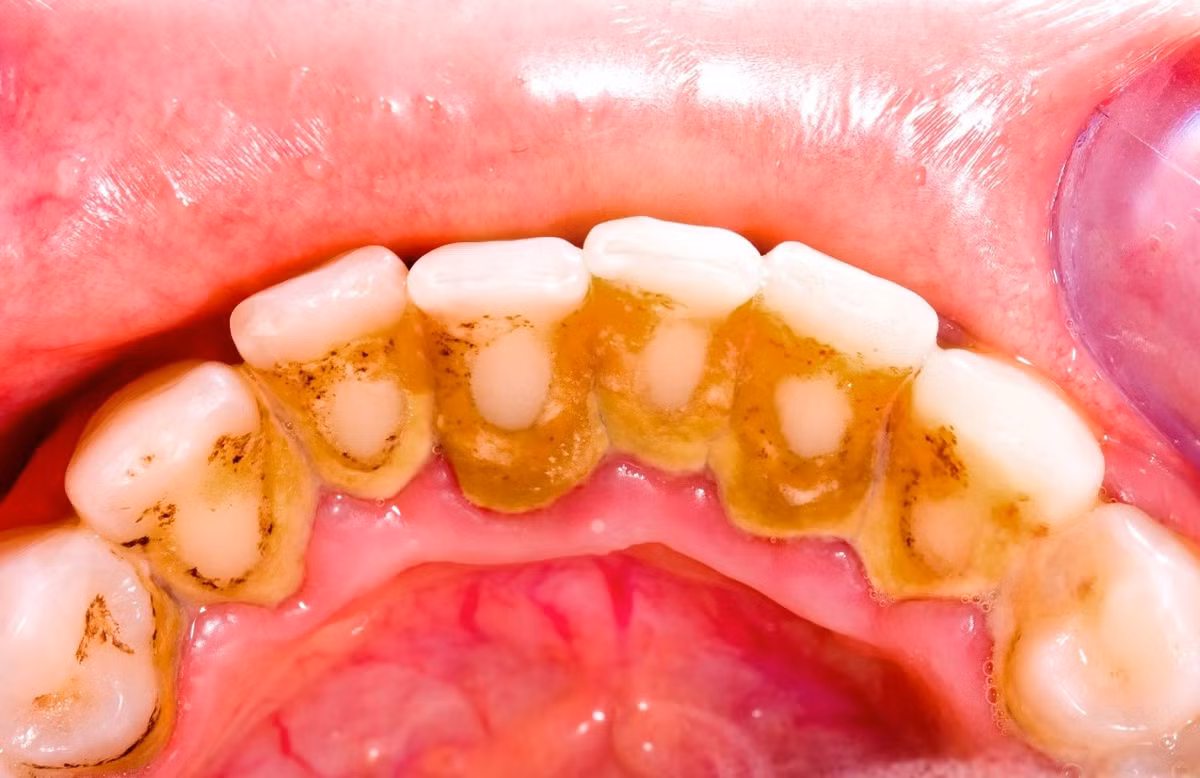

Cao răng không ngờ lại là thủ phạm gây nhiều bệnh thế này

Cao răng (hay vôi răng) do cặn vụn dư thừa của thực phẩm bám dính vào thân răng, chui xuống nướu răng. Từ đó hình thành mảng bám, theo thời gian phản ứng với những vi khuẩn, nước bọt... trong miệng lắng đọng lại, tạo thành cao răng.

Tốc độ tạo cao răng ở mỗi người một khác, sự hình thành của nó bị ảnh hưởng của những thành phần có trong nước bọt, thói quen ăn uống, thói quen vệ sinh răng miệng.

Nguyên nhân dẫn đến cao răng là do thói quen vệ sinh răng miệng: Không chải răng thường xuyên, không dùng chỉ nha khoa, không lấy cao răng định kỳ 6 tháng/lần; ăn nhiều thức ăn ngọt (bánh kẹo, đồ uống có đường sẽ khiến các mảng bám hình thành nhanh hơn, tạo điều kiện thuận lợi cho vi khuẩn hoạt động gây nhiều bệnh tật về răng miệng). Những người hút thuốc lá, nghiện trà, cà phê,... cũng là nhóm đối tượng chịu sự tấn công của vôi răng - mảng bám nhiều bất thường.

Tác hại của cao răng

Mảng bám cao răng chứa 400 loài vi khuẩn khác nhau và hàng tỷ vi trùng sinh sôi trong mỗi mg mảng bám. Hầu hết các vi trùng có hại và chúng có thể gây tổn hại cho răng, nướu răng khi nó tập trung thành lớp dày. Chính vì thế, cao răng là một trong những nguyên nhân gây bệnh ở lợi và quanh răng. Cao răng có thể dẫn đến các bệnh như viêm lợi, với các biểu hiện đánh răng chảy máu, miệng có mùi hôi. Cao răng cũng có thể gây viêm nha chu dẫn đến tiêu xương làm răng bị đau, ê buốt khi ăn uống, nặng hơn có thể gây lung lay và rụng răng. Cao răng còn gây ra viêm tủy ngược dòng. Ngoài ra, khi miệng chứa nhiều vi khuẩn từ cao răng, khi nhai và nuốt thức ăn, vi khuẩn sẽ theo thức ăn đi vào đường ruột và xâm nhập cơ thể từ đường tiêu hóa.

Cao răng là một trong những nguyên nhân gây bệnh ở lợi và quanh răng.